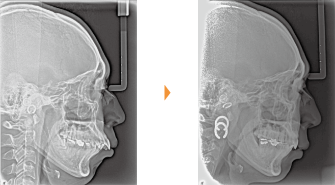

| 主訴 | 噛み合わせが逆、八重歯 |

| 年齢・性別 | 20歳 / 女性 |

| 治療方針 | オトガイの突出感が強く、前歯だけでなく臼歯部も反対咬合。低位舌が認められる。顔貌改善には外科矯正が適応と考えられたが本人が希望しなかったため、MFTを行ったのち上顎拡大、上下マルチブラケット装置のみで治療を行った。左上中切歯に打撲の既往あり。 |

| 抜歯部位 | 上下顎左右第3大臼歯(計4本) |

| 使用装置 | クウォードヘリックス、マルチブラケット装置 |

| 治療期間 | 25か月 |

| リテーナー | 上顎インビジブル、下顎スプリングリテーナー |

| 費用 | 825,000円(税別) |